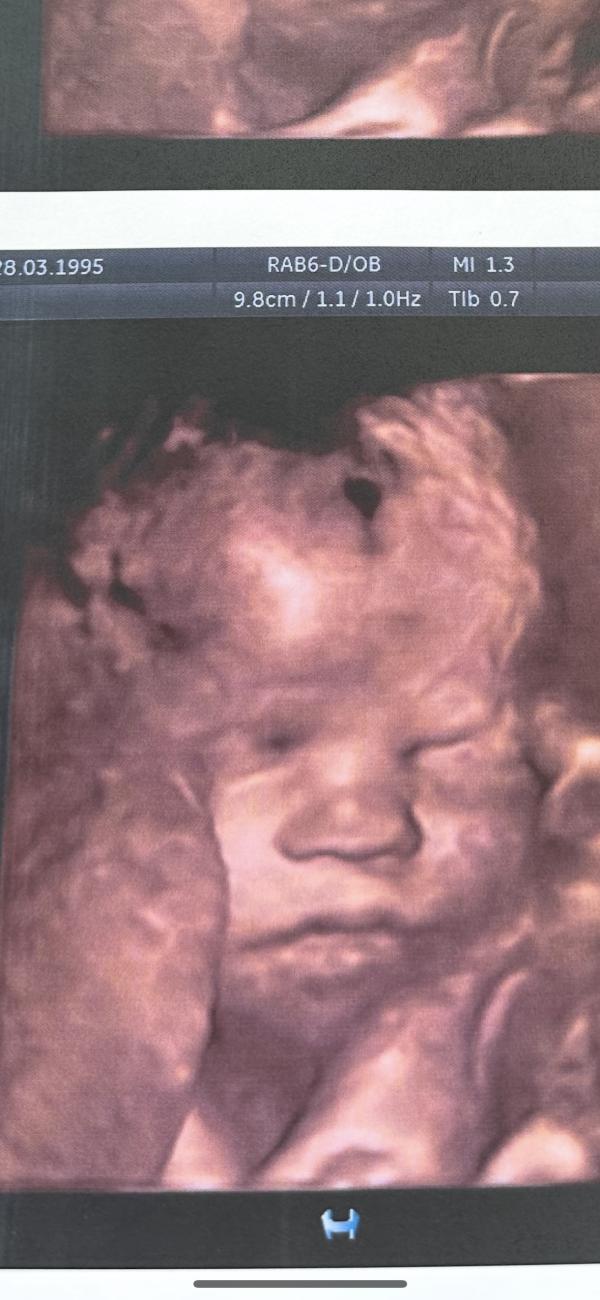

А сейчас ляля уже такая большая🥹прям новорожденный человечек❤️даже шевелюра говорит у неё уже есть 😍

P.S. теперь сижу и Сравниваю: похожи ли с Алиской 🤭предпоследнее фото Алиска, последнее фото ляля сегодня ))

Губы одинаковые ))